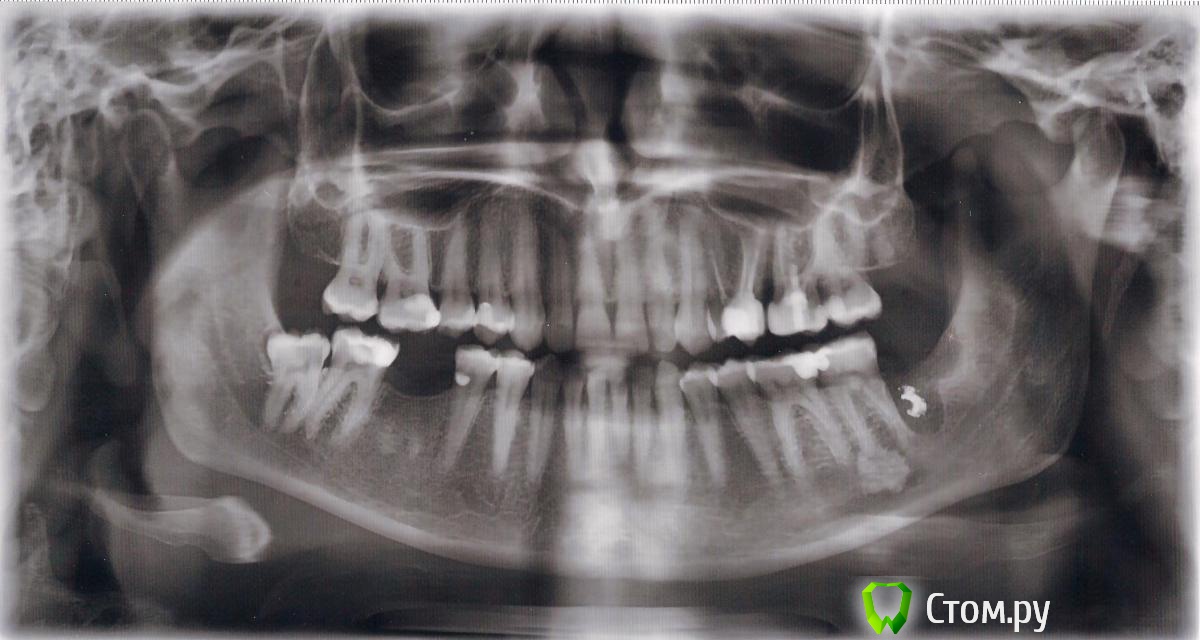

Ольга* Опубликовано 3 апреля, 2014 Автор Поделиться Опубликовано 3 апреля, 2014 может быть с содержанием йода, или еще какого антисептика, а снимка до удаления у вас нет?Да йод скорее всего. Я до сих пор его чувствую, не знаю должно так быть или нет, прошло уже 2 недели. Вот снимок до лечения. Ссылка на комментарий

Ольга* Опубликовано 4 апреля, 2014 Автор Поделиться Опубликовано 4 апреля, 2014 Может и не йод, но явно это не остатки зуба или стенки лунки, это то что док туда положил.Спасибо за ответы. Вы меня немного успокоили. У меня ещё один вопрос. Я собираюсь ставить имплант на место нижней правой шестерки. Достаточно ли там кости для него? Нужно ли мне будет удалять второй зуб мудрости или можно как-то обойтись без удаления? Второй раз на эту процедуру мне будет сложно решиться. Может его можно как-то пролечить? Если нельзя, то может быть посоветуете какие-нибудь гуманные способы удаления этих зубов. У меня есть КТ, только не знаю как его загрузить. Ссылка на комментарий

red_butler Опубликовано 4 апреля, 2014 Поделиться Опубликовано 4 апреля, 2014 (изменено) Спасибо за ответы. Вы меня немного успокоили. У меня ещё один вопрос. Я собираюсь ставить имплант на место нижней правой шестерки. Достаточно ли там кости для него? Нужно ли мне будет удалять второй зуб мудрости или можно как-то обойтись без удаления? Второй раз на эту процедуру мне будет сложно решиться. Может его можно как-то пролечить? Если нельзя, то может быть посоветуете какие-нибудь гуманные способы удаления этих зубов. У меня есть КТ, только не знаю как его загрузить.По высоте место есть, ширину нужно смотреть на кт или на очном осмотре. Выкладывайте кт http://forum.stom.ru/topic/10677-kak-vylozhit-kt-na-saite/Вторую "восьмерку" все таки лучше удалить, это можно сделать за один прием с имплантацией, в идеале под седацией. Каких либо технических проблем с удалением не вижу, при правильной подготовке и квалифицированном подходе все будет хорошо Изменено 4 апреля, 2014 пользователем red_butler Ссылка на комментарий